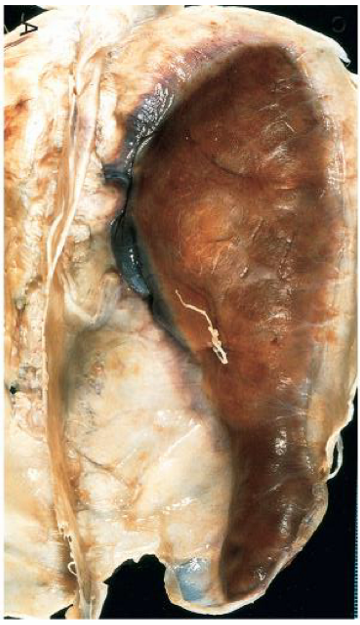

describe the etiology of a pale/bland infarct in the condition seen in the image

thrombotic/ischemic stroke: HTN → atherosclerosis → unstable plaque → thrombosis → **bland infarct**

describe the etiology of a red infarct in the condition seen in the image

embolic stroke atrial fibrillation + mural thrombus in left heart → legs (DVT) or BRAIN (red infarct)

the most commonly affected vessel in the condition seen in the image is the \_\_\_\_

the most commonly affected vessel in the condition seen in the image is the **middle cerebral artery**

describe the appearance of the brain seen in the condition in the image: early stroke: \_\_\_\_ old stroke: \_\_\_\_

early stroke: **red infarct** old stroke: **gliosis, scarring**

in the condition seen in the image, ____ is seen during 12-24 hours

in the condition seen in the image, **coagulative necrosis** is seen during 12-24 hours

in the condition seen in the image, \<24 hours is considered ____ while \>24 hours is considered \_\_\_\_\_

in the condition seen in the image, \<24 hours is considered **TIA** while \>24 hours is considered **stroke (permanent neurological deficit)**

in the condition seen in the image, ____ is seen after \>48 hours

in the condition seen in the image, **microglia → liquefactive necrosis** is seen after \>48 hours

in the condition seen in the image, ____ is seen after 2 weeks

in the condition seen in the image, **astrocytes → gliosis** is seen after 2 weeks

the condition seen in the image can be caused by long-standing _____ causing ____ which leads to _____ aneurysm

the condition seen in the image can be caused by long-standing **benign HTN** causing **hyaline arteriosclerosis** which leads to **Charcot Bouchard** **aneurysm**​

describe the 2 types of infarcts that HTN can lead to the condition seen in the image

* **slit hemorrhages** * hemorrhages thought to be secondary to microaneurysm rupture (Charcot Bouchard aneurysm) * **lacunar infarcts** * bland infarcts, thought to be secondary to thrombosis of a vessel w/ arteriosclerotic changes

describe the 4 types of vascular malformations that can lead to the condition seen in the image

* arterio-venous malformation = greatest potential for hemorrhage * cavernous hemangiomas * capillary telangiectasias * venous angiomas

cerebral amyloid angiopathy is a disease in which the same amyloidogenic peptides seen in ____ accumulate in the walls of ____ and can lead to the condition seen in the image

cerebral amyloid angiopathy is a disease in which the same amyloidogenic peptides seen in **Alzheimer's** accumulate in the walls of **medium and small caliber meningeal and cortical vessels** and can lead to the condition seen in the image

the most common location for the condition seen in the image is \_\_\_\_

the most common location for the condition seen in the image is **the basal ganglia**

describe the symptoms of the condition seen in the image when it occurs in the most common location

**basal ganglia = contralateral hemiparesis + sensory loss**